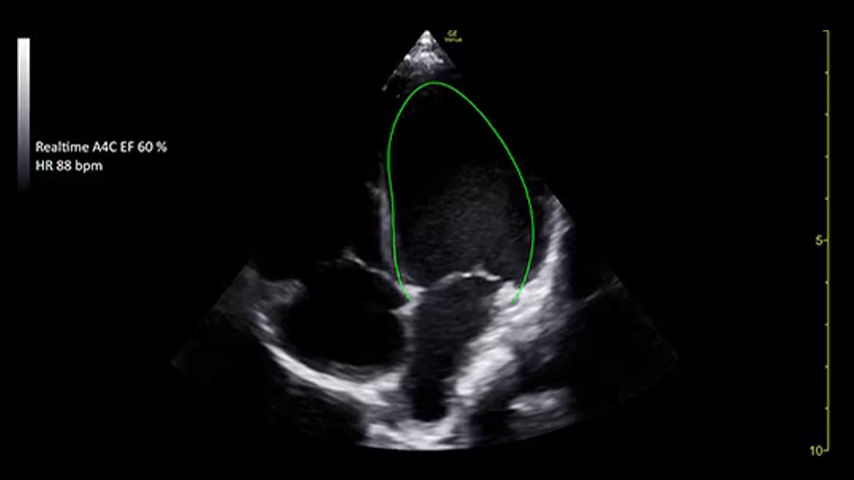

Access accurate, instant, and rapidly updating results with Real-Time EF

Capture precise results instantly without requiring ECGs through Real-Time EF*, an AI tool that continuously calculates real-time ejection fraction during live scanning in apical 4CH view.